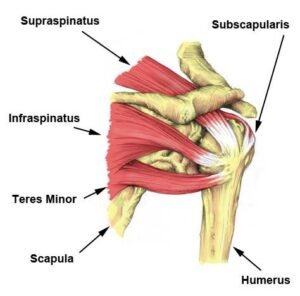

The supraspinatus tendon is a critical component of the rotator cuff, a group of muscles and tendons that surround the shoulder joint. Understanding the anatomy of the supraspinatus tendon is essential for comprehending its function and the role it plays in shoulder movement and stability.

- Origin : The supraspinatus tendon originates from the supraspinatus fossa, a concave depression in the scapula (shoulder blade), above the spine of the scapula. It arises as a thickening of the superior part of the fossa.

- Pathway : From its origin, the tendon courses laterally beneath the acromion, the bony prominence at the top of the shoulder. It passes through a space known as the subacromial space, forming the superior part of the rotator cuff.

- Insertion : The supraspinatus tendon inserts onto the greater tubercle of the humerus, which is a prominence on the upper part of the arm bone (humerus). It forms a critical connection between the muscle and the bone, facilitating the transmission of forces during shoulder movements.

The primary functions of the supraspinatus tendon are closely tied to its role within the rotator cuff and the overall mechanics of the shoulder joint:

- Abduction of the Arm : The supraspinatus muscle, activated by its tendon, is a key initiator of arm abduction. Abduction refers to the movement of lifting the arm away from the body’s midline. This action is crucial for various daily activities involving overhead movements.

- Stabilization : Along with the other rotator cuff muscles, the supraspinatus tendon plays a vital role in stabilizing the shoulder joint during movements. It helps keep the head of the humerus securely in the glenoid cavity of the scapula, preventing dislocations and ensuring smooth articulation.

- Assistance in Rotational Movements : While the primary action is abduction, the supraspinatus also contributes to other shoulder movements, including external rotation. This rotational capability enhances the versatility of the shoulder joint.